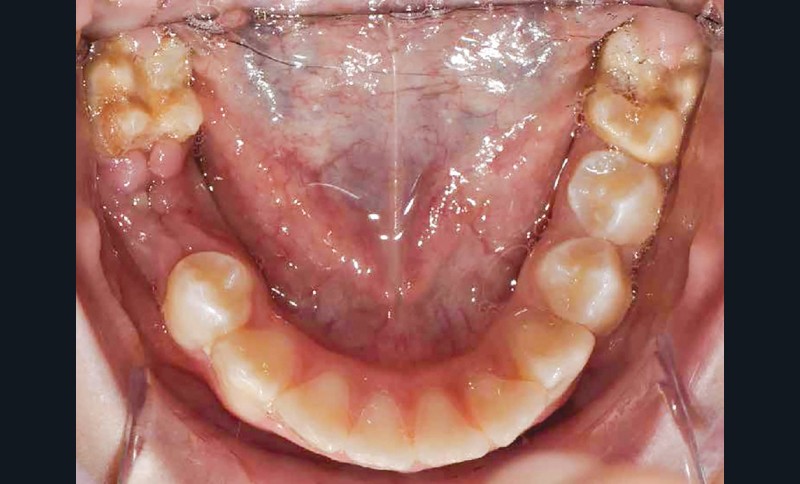

Lisa est une jeune patiente de 10 ans, atteinte d’une MIH sévère sur les premières molaires mandibulaires 36 et 46 (fig. 1 et 2). Elle présente une sensibilité exacerbée au froid en regard des zones molaires entraînant un brossage approximatif.